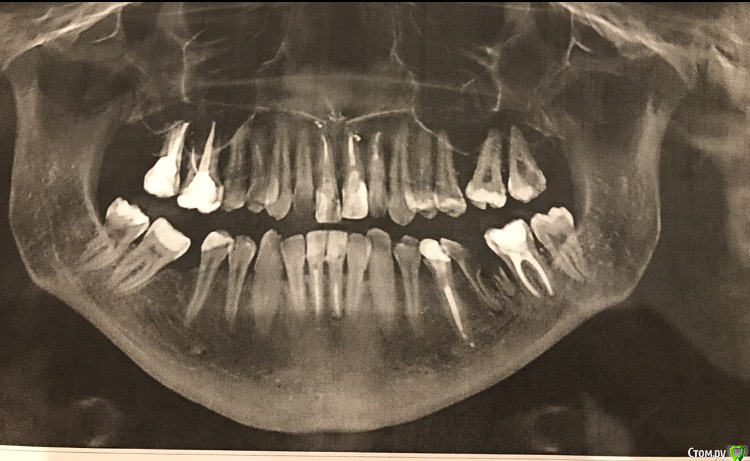

Ситуация сложная, что вполне видно на фотографиях.

верхние 1,1,2 штифты

нижние 1,1 штифты. 6-ка слева под удаление. 5-ка сверху нависает.

7-ка верх слева удалена, на ее месте стоит 8-ка (пульпит)

6-ка справа внизу удалена, 8ка справа сверху удалена.

Много депульпированных зубов, почти везде пломбы.

Имеется щелчок в суставе, но сустав не болит. Щелчки периодичные, не постоянные.

Своему бы пациенту в такой ситуации я бы назначила:

1) КТ и консультацию терапевта с описанием прогноза всех зубов

2)  удаление зубов мудрости, удаление нижнего левого шестого

3) ортодонтическое лечение на брекет-системе с раскрытием места под левый верхний шестой

п.с. эндодонтически пролеченные зубы также поддаются перемещению с помощью брекетов.

А трещины на эмали у Вас скорее всего вследствие перегрузки зубов, которая в свою очередь возникла из-за имеющихся деформаций зубных рядов.